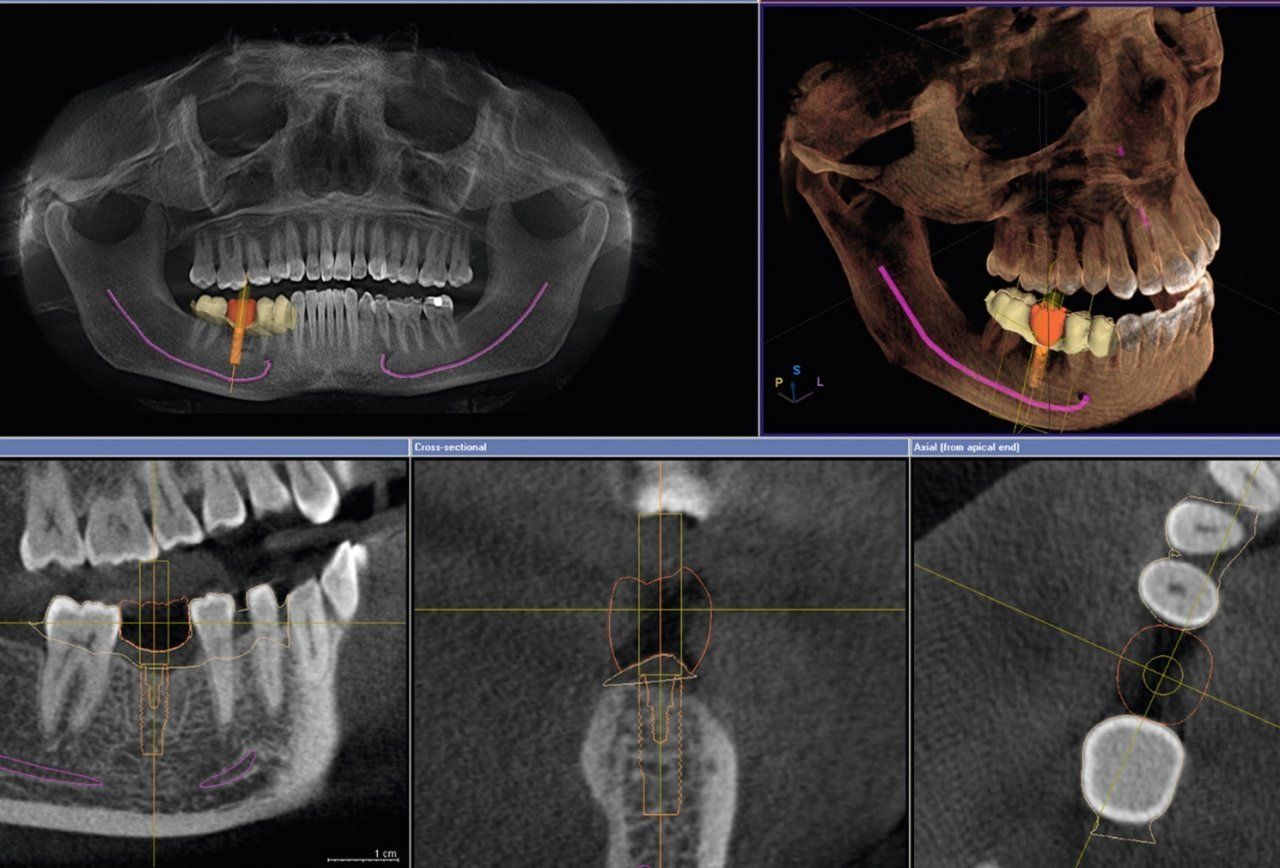

Als eine der wenigen zahnärztlichen Praxen in Bremen bieten wir modernstes digitales 3D-Röntgen an. Die digitale Volumentomographie (DVT) ist die zur Zeit modernste und strahlenärmste Aufnahmetechnik für Fragestellungen im Bereich von Hals und Kopf, den Zähnen und dem Kiefergelenk. So ist z.B. eine sichere Behandlungsplanung auch in sehr schwierigen Fällen möglich. Auch für die moderne Endodontie (Wurzelbehandlung) ergeben sich durch die DVT-Aufnahmetechnik neue, viel genauere diagnostische Möglichkeiten, z.B. die projektionsfreie maßstabsgetreue Darstellung der einzelnen Wurzelspitzen und der Kanalanatomie. Unklare diffuse Zahnbeschwerden können evtl. erst durch DVT geklärt werden. Ein einziger Durchlauf mit einer direkten Volumenaufnahme reduziert die Strahlenbelastung gegenüber dem Computertomogramm (CT) um mindestens 50 bis zu 90 %. Parallel kann eine bis zu 4-mal höhere Bildauflösung erreicht werden. Störende Fremdkörper wie z.B. Zahnmetall, welche die Qualität der Befundung beeinträchtigen würden, können ausgeblendet werden.

Die besondere Aufnahmetechnik erlaubt zudem die unmittelbare Berechnung und Darstellung als 3D-Volumen. Die Aufnahmezeit liegt dabei bei nur ca. 18 Sekunden - mit Bearbeitung der Datensätze ist die Untersuchung in nur 2 Minuten abgeschlossen. Die DVT-Aufnahme kann dem Patienten als Datenträger mitgegeben werden. Die Abrechnung erfolgt über die Gebührenordnung für Ärzte (GOÄ) und ist von den privaten Krankenkassen voll erstattungsfähig.